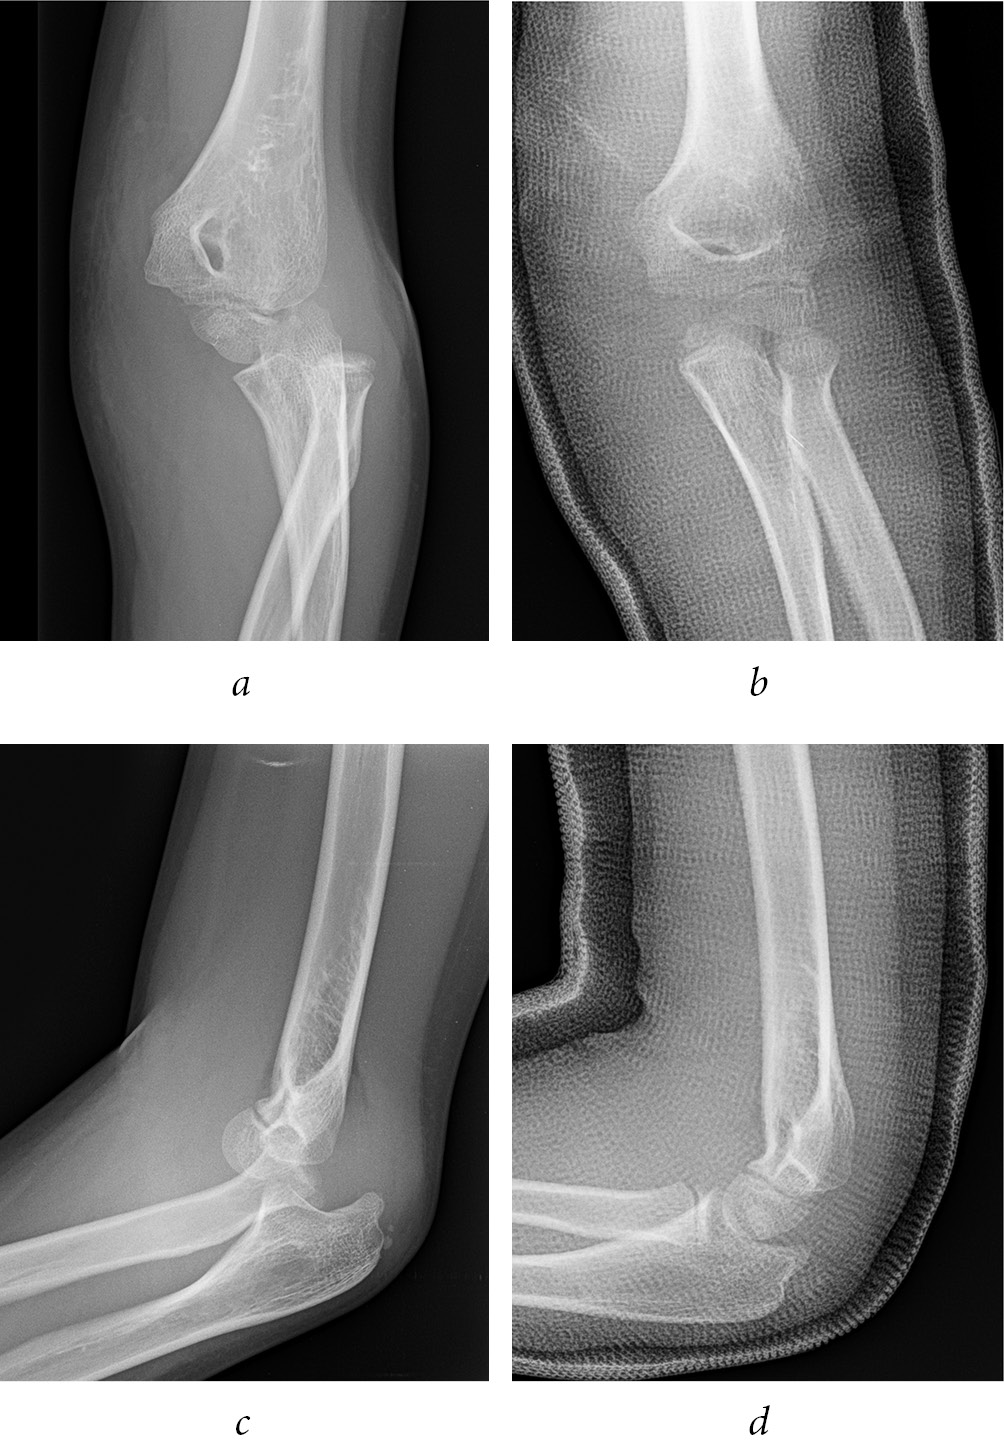

At the last follow-up no patients presented axial deformity of the upper limb or instability of the elbow. The mean elbow ROM ranging from 2° of extension to 140° of flexion. All patients showed a complete forearm prono-supination. No patient had limitation in extension while 5 patients reported 5° of limitation in flexion compared to the unaffected side. The MEPS score was excellent in 12 patients and good in 1 (caused by pain) with mean MEPS score of 98.8 (range 85–100). The mean value of the VAS score was 1 (range 0–2). Six patients presented with preoperative paresthesia in the ulnar nerve field but all of them reported a complete and spontaneous recovery after a mean of 4.3 months (range 1–6 months) and all the patients showed no nerve symptoms at the final follow-up. No patients reported post-operative ulnar nerve palsy or a worsening of the pre-existing ones. Four patients complain hyperesthesia of the surgical scar and at ME palpation at the last follow-up. The X-rays performed at the final follow-up were evaluated by an orthopaedic surgeon. They showed signs of healing in 11 patients and signs of nonunion in two patients (15.3%) but these were totally asymptomatic at the clinical examination. The radiographic outcome evaluated by Skak classification showed no deformity in 4 (30.7%) while 1 patient reported a double contour deformity (7.7%), 1 patient reported hypoplasia of ME (7.7%) and 5 cases had a ME hyperplasia (38.4%)(Fig. 5). None of the deformities interfered with day-to-day elbow function. One patient (7.7%) developed heterotopic ossification around the elbow joint without clinical relevance. All patients returned to their sporting activities at a mean of 5.4 months after surgery (range 3–12 months). Average surgical time (from incision to postoperatively cast) in our group of patients was 70 minutes (range 35–120 minutes). Average intraoperative fluoroscopy time was 33 seconds (range 8–107 seconds). One patient (7.7%) reported a superficial surgical wound infection caused by S. Aureus which was treated with an oral antibiotic medication without further surgery. No other complication was found (Table 2).

Fig. 5. The common deformity pattern presented at last follow up X-ray in our patients: a — non-union; b — double contour; c — hyperplasia; d — hypoplasia

MEF with intra-articular elbow entrapment is an absolute indications for surgical treatment [7], multiple types of surgical approach have been reported in the literature [15, 16, 17] although currently the most used surgical treatment of MEF is an open reduction and fixation with cannulated screw [1]. The surgical technique reported in this article consists on an open reduction of the MEF with intra-articular elbow entrapment, through posteromedial incision, without routinely exploration of the ulnar nerve, and fixation of the bony fragment with two crossing bicortical 1.5 mm k-wires. This approach showed satisfactory clinical outcomes with excellent score in the MEPS in 12 patients and good score in1 patient (mean MEPS 98.8), without limitation of elbow range of motion. These results were similar to the outcome reported in the literature [18, 19]. In particular, Dodds et al. [18] reported a total of 11 patients with mean MEPS was 99.5 while Tarallo et al. [19] in their study reported a MEPS score excellent in all patients (mean MEPS 96.3). The X-rays performed at the final follow-up showed healing in 11 patients and signs of nonunion in 2 patients (15.3%) which were totally asymptomatic. Our results of fracture healing were similar but lower with other authors [20, 21] who used the technique with screws, in particular Dodds et al. and Tarallo et al. reported union in all patients at final X-rays. The radiographic outcome evaluated by Skak classification showed no deformity in 4 (30.7%) while 1 patient reported a double contour deformity (7.7%), 1 patient reported hypoplasia of ME (7.7%) and 5 cases had a ME hyperplasia (38.4%). None of the deformities interfered with day-to-day elbow function. In our opinion the nonunion and the deformity of ME after surgical treatment may be caused to use of k-wire that do less compression compared to cortical screw and therefore make ME fracture fragment more mobile but there are studies that have shown rates of greater hyperplasia with screws compared to wires [20]. No study found clear correlation between method of treatment or type of deformity of ME.